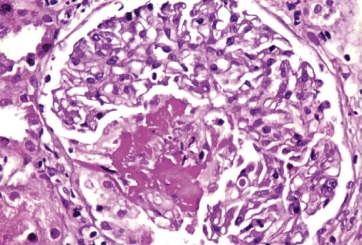

Biopsy is another supportive tool that can be confirmatory, particularly in cases with renal, pulmonary, or skin involvement, but treatment should not necessarily be delayed simply to get a biopsy.

Renal biopsy in a patient with severe active AAV showing